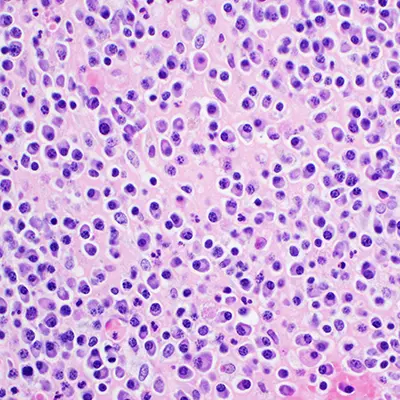

La hematología es la especialidad que se dedica al tratamiento de los pacientes con enfermedades de la sangre. Su campo de actuación es el diagnóstico, tratamiento, estudio e investigación de la sangre y los órganos hematopoyéticos (médula ósea, ganglios linfáticos y bazo) tanto sanos como enfermos.